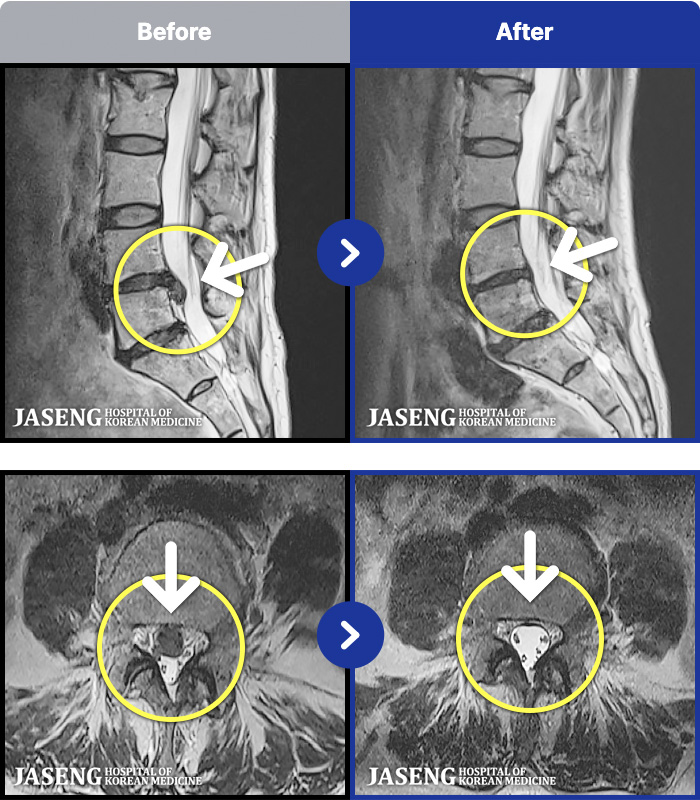

MRI ġ

1,237 MRI ũ ʸ Ȯϼ.